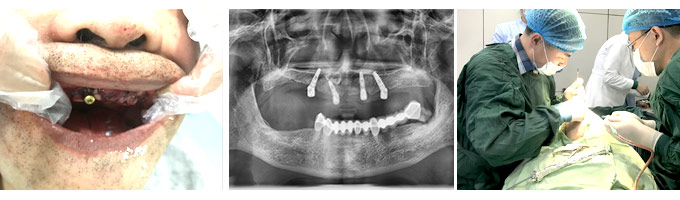

经过详细的口腔检查后,我发现刘大爷的牙槽骨萎缩严重,还患有骨质疏松。牙周病会让牙槽骨萎缩、骨质流失、牙松脱落。牙周病也会影响种植牙成活率,应先治牙周病,再种牙。

做完牙周治疗,我们为刘大爷制定了即刻种植方案,这个方案是专为50岁以上的中老年人设计的,最大的优势是对骨量的要求不高,不需植骨也能种牙,尤其适合牙槽骨条件不好,有骨质疏松的人群,且全程微创无痛,治疗时间短。术后,刘大爷表示后悔没早点来种牙,现在晚年幸福终于有了很大的保障,想吃什么就吃什么。

即刻种植牙,是康贝佳口腔的特色种牙方式。它的特点是对骨量的要求不高,不需植骨也能种牙。而且当天种牙当天就有牙用。因为采用了体积更小的植体,医生在植入牙槽骨时更为精准;骨愈合面减小,骨结合也自然更快,这让种植牙手术变得简单、轻松!